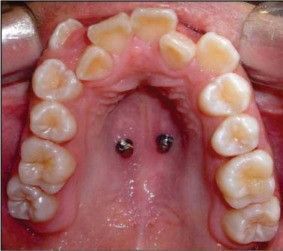

Los ortoimplantes (mini implantes para ortodoncia) son pequeños “tornillos” de fijación temporal que se colocan anclados en el hueso durante el tratamiento de ortodoncia. Estos implantes permiten que el especialista realice casi todos los movimientos dentales sin que la fuerza ejercida recaiga sobre los dientes, lo que optimiza el tiempo de tratamiento y reduce el número de aparatos utilizados en la boca. Al finalizar el tratamiento, los ortoimplantes se retiran sin dejar secuelas.

Colocación y retiro de ortoimplantes